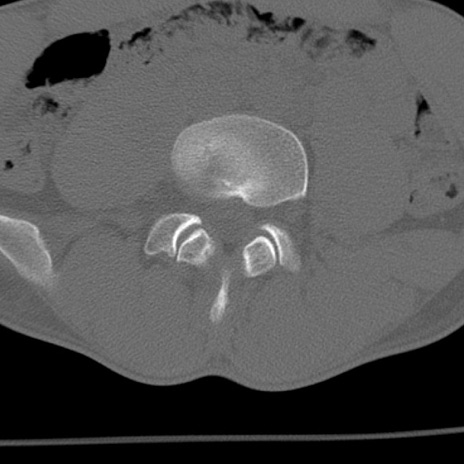

症例3 腰椎CT(横断像)

腰椎CT